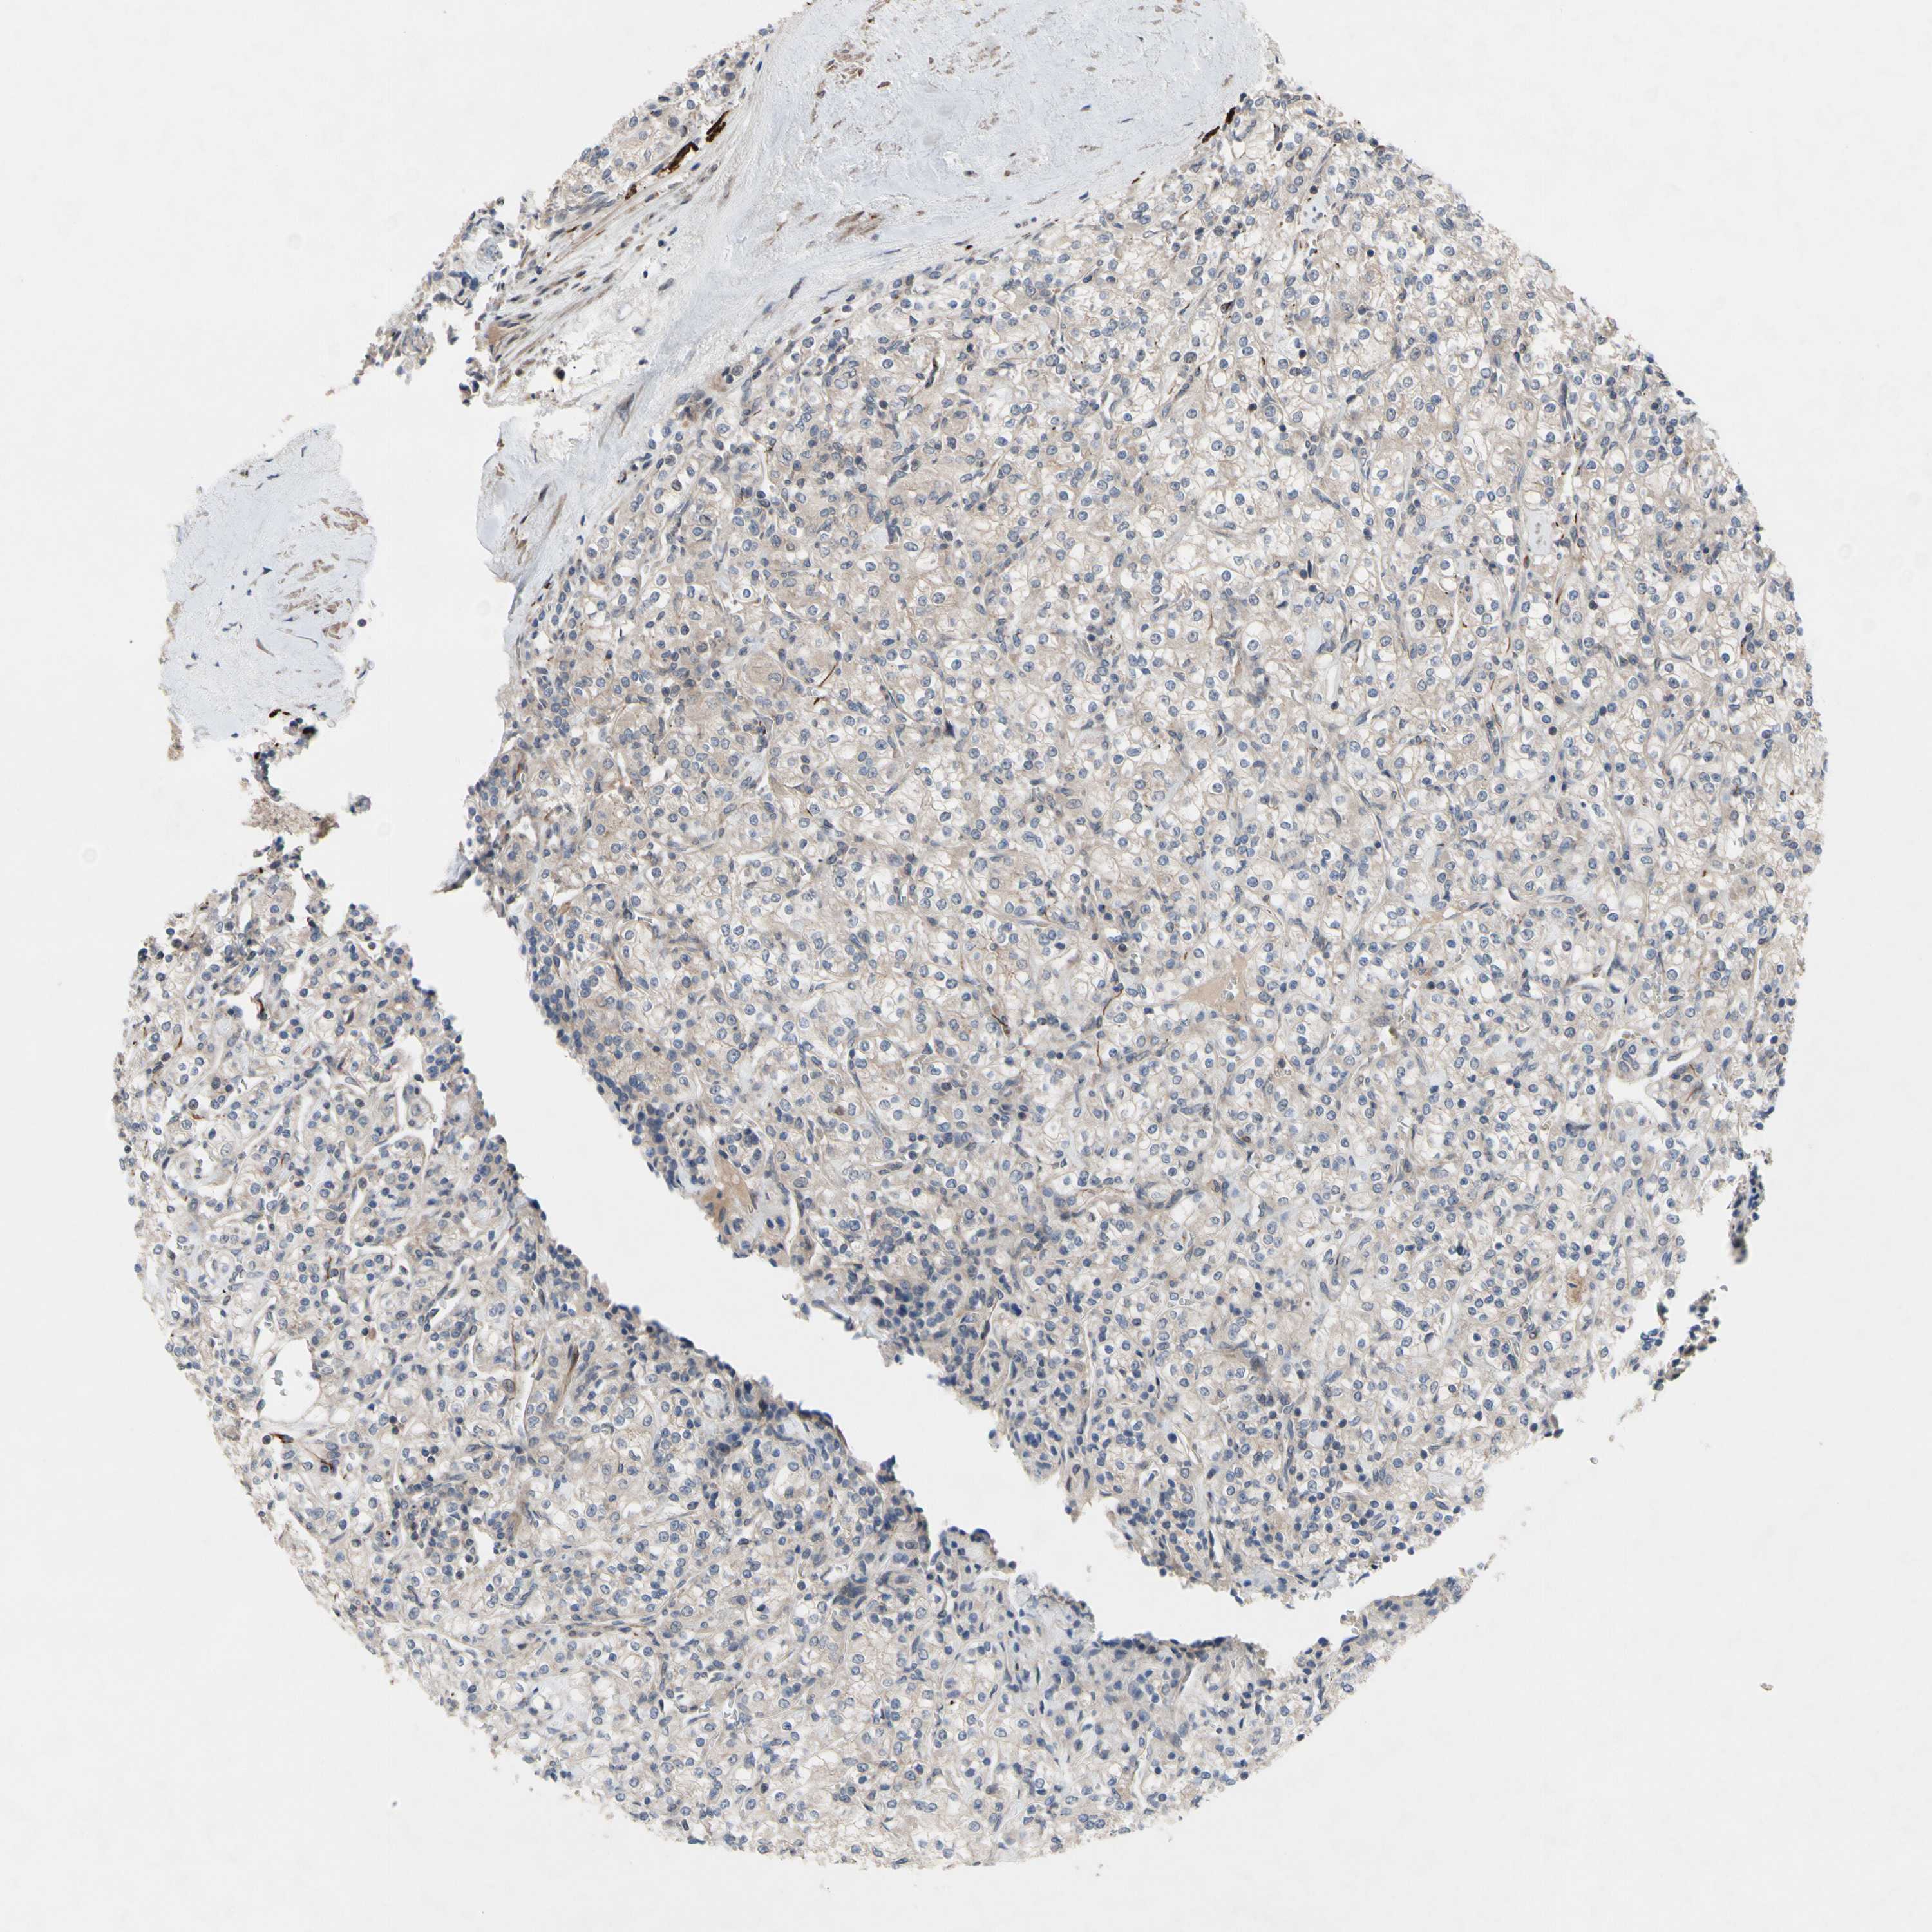

KIDNEY RENAL CLEAR CELL CARCINOMA (VALIDATION) - Interactive survival scatter ploti

The Survival Scatter plot shows the clinical status (i.e. dead or alive) for all individuals in the patient cohort, based on the same data that underlies the corresponding Kaplan-Meier plots. Patients that are alive at last time for follow-up are shown in blue and patients who have died during the study are shown in red.

The x-axis shows the expression levels (FPKM) of the investigated gene in the tumor tissue at the time of diagnosis. The y-axis shows the follow-up time after diagnosis (years). Both axes are complimented with kernel density curves demonstrating the data density over the axes. The top density plot shows the expression levels (FPKM) distribution among dead (red) and alive patients (blue). The right density plot shows the data density of the survived years of dead patients with high and low expression levels respectively, stratified using the cutoff indicated by the vertical dashed line through the Survival Scatter plot. This cutoff is automatically defined based on the FPKM cutoff that minimizes the p-score. The cutoff can be changed by dragging the vertical line or by entering a cutoff value in the square labeled "Current cut-off".

Under the Survival Scatter plot the p-score landscape (black curve; left axis) is shown together with dead median separation (red curve; right axis). Dead median separation is the difference in median mRNA expression between patients who have died with high and low expression, respectively. It is calculated as follows: median FPKM expression of dead patients with high expression - median FPKM expression of dead patients with low expression. This is intended to aid the user in visually exploring custom cutoffs and the associated p-scores and dead median separation.

Individual patient data is displayed and can be filtered by clicking on one or more of the category buttons on the top of the page. Categories describing expression level and patient information include: high, low, alive, dead, female, male and tumor stages. The scale of the x-axis can be toggled between linear and log-scale by clicking on the "x log" button. Mouse-over function shows TCGA ID, patient information and mRNA expression (FPKM) for each patient.

& Survival analysisi

Kaplan-Meier plots summarize results from analysis of correlation between mRNA expression level and patient survival. Patients were divided based on level of expression into one of the two groups "low" (under cut off) or "high" (over cut off). X-axis shows time for survival (years) and y-axis shows the probability of survival, where 1.0 corresponds to 100 percent.

OAZ1 is not prognostic in Kidney Renal Clear Cell Carcinoma (validation)

: 167.09

Average pTPM 174.5

Number of samples 100